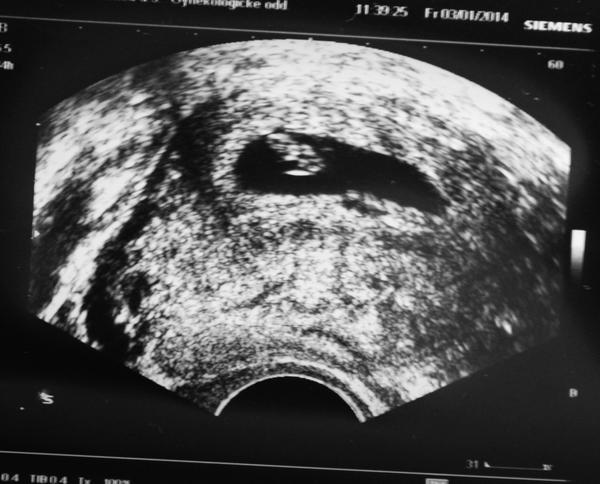

@barborynka krásná fotka, jen ať mrňousek krásně roste!